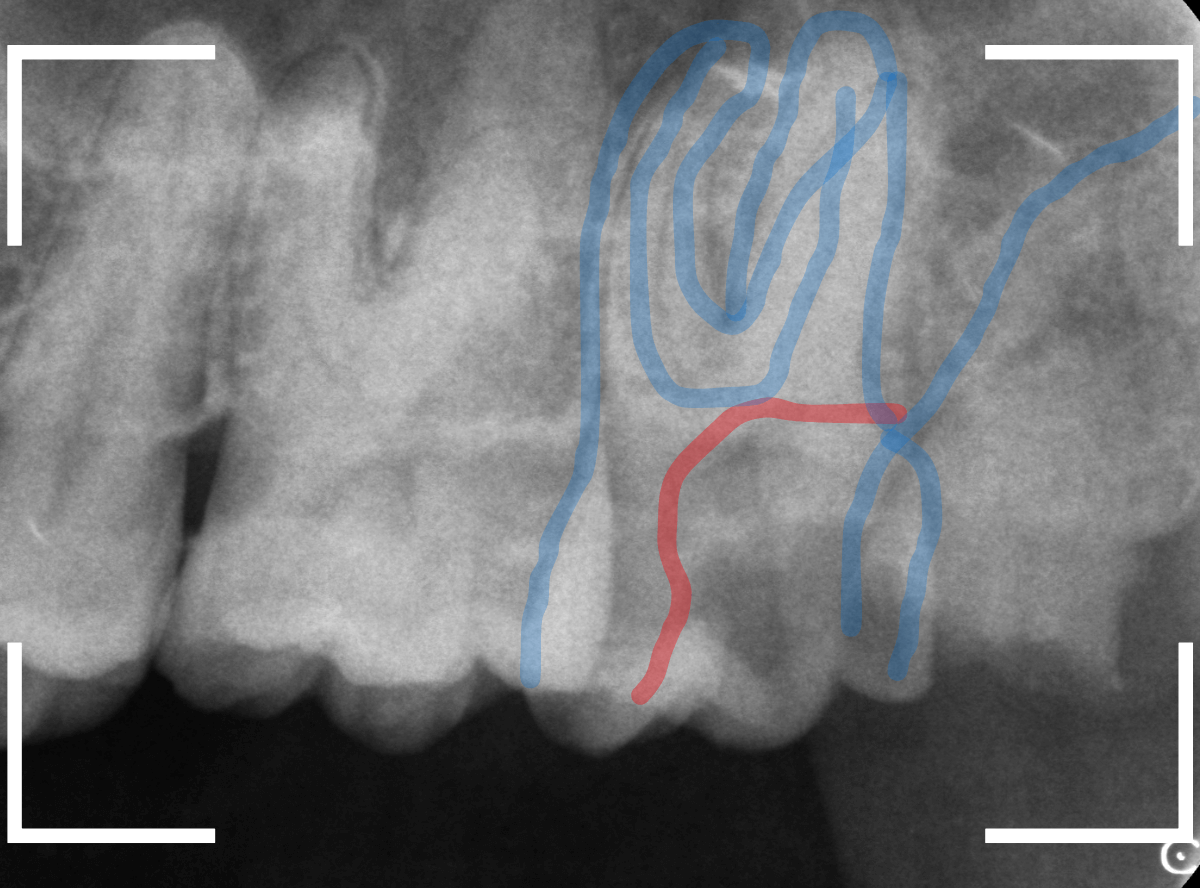

レントゲン写真で確認します。

青い線が歯の形と神経です。

赤い線が、虫歯です。

初見でも想像がつきましたが、かなり虫歯がひどく、治療して再び噛む事が出来るようにするのが不可能で、抜歯をする事になりました。

患者さんも、自覚があったようで、すぐに同意いただきました。